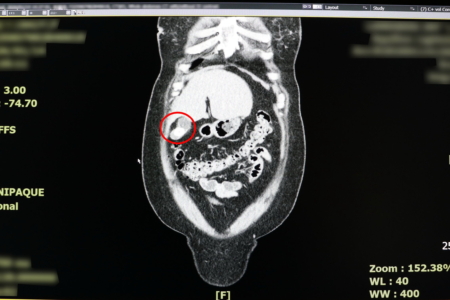

【大紀元2026年03月04日訊】(大紀元記者徐乃義台灣桃園報導)反覆上腹部疼痛時,別再以為只是胃病,當心是「體內未爆彈」膽囊炎作祟!一名38歲女性日前因持續2天劇烈上腹痛,先後到診所與地區醫院就診,皆被診斷為胃炎,服藥與打止痛針仍未改善,求診聯新國際醫院急診室,經朱海慶醫師詢問病史與電腦斷層檢查,會診一般外科張堯任醫師,確診為急性膽囊炎。

病患就醫時已出現發燒,白血球與發炎指數攀升的情況,張堯任建議應儘快手術。病患考量自身工作需頻繁搬運重物,且希望快速復工,選擇單孔達文西手術切除膽囊,術後當天即可下床走動並正常飲食,隔天返家休養,迅速重返職場。